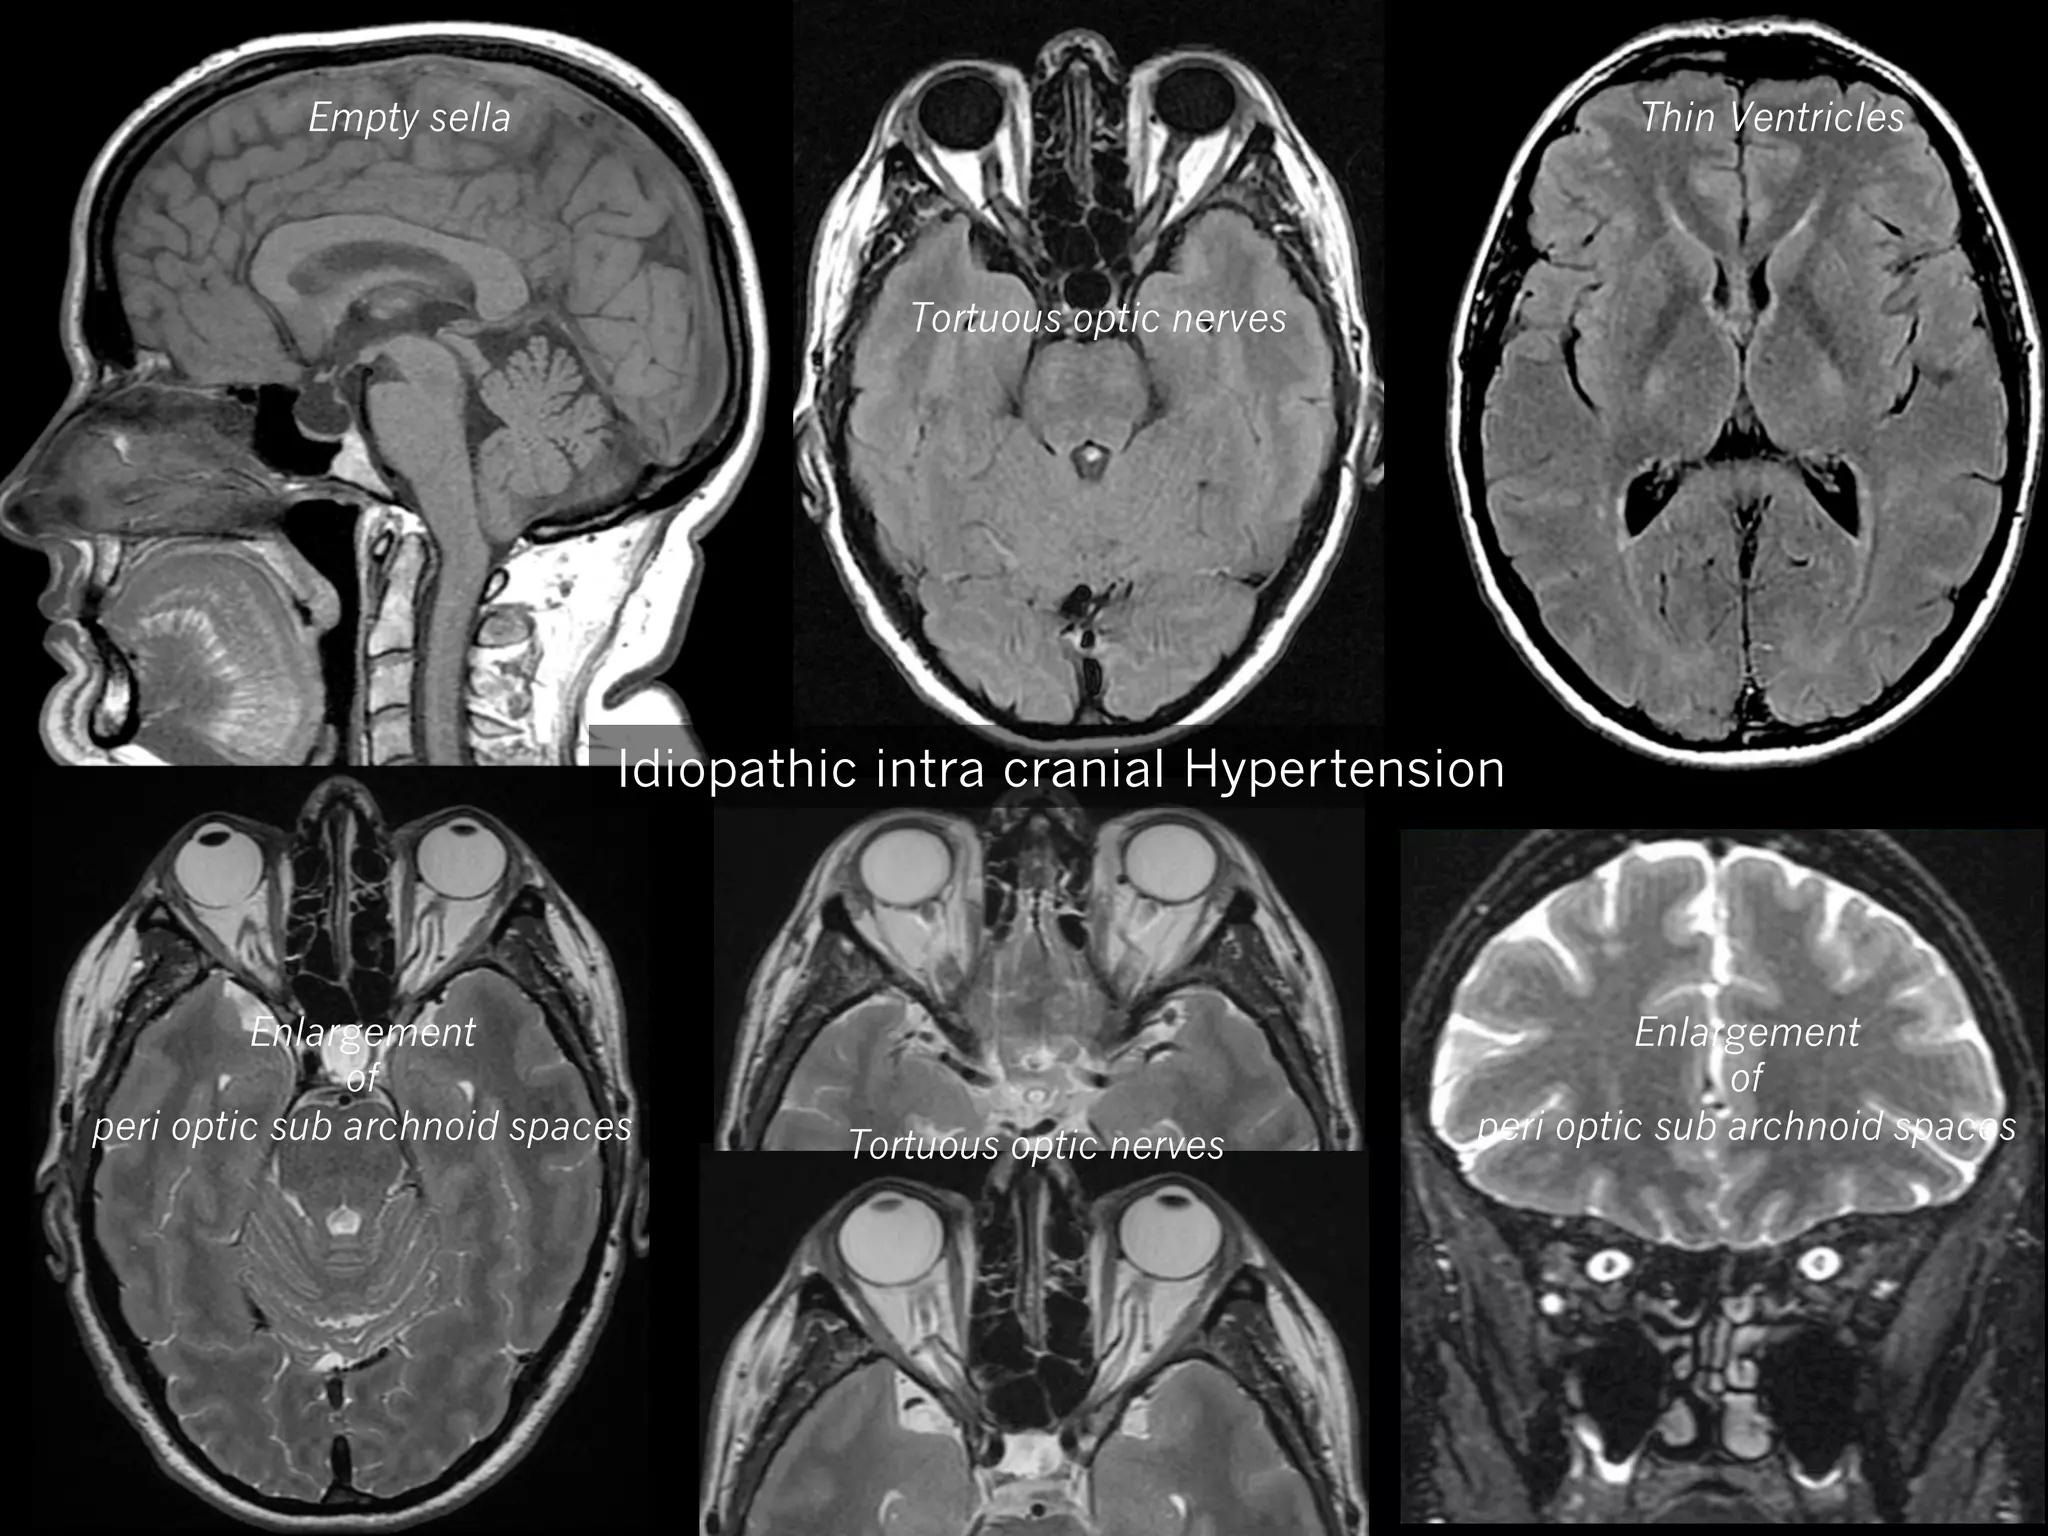

Empty sella

Thin Ventricles

Tortuous optic nerves

Idiopathic intra cranial Hypertension

Enlargement

of

peri optic sub archnoid spaces

MRI

Axial FLAIR

Axial (or frontal) T2w : orbital exploration +++

—  Tortuous optic nerves (> 7O%)

—  Enlargement of peri optic subarachnoid space (70%)

—  Flattening of posterior globe (45%)